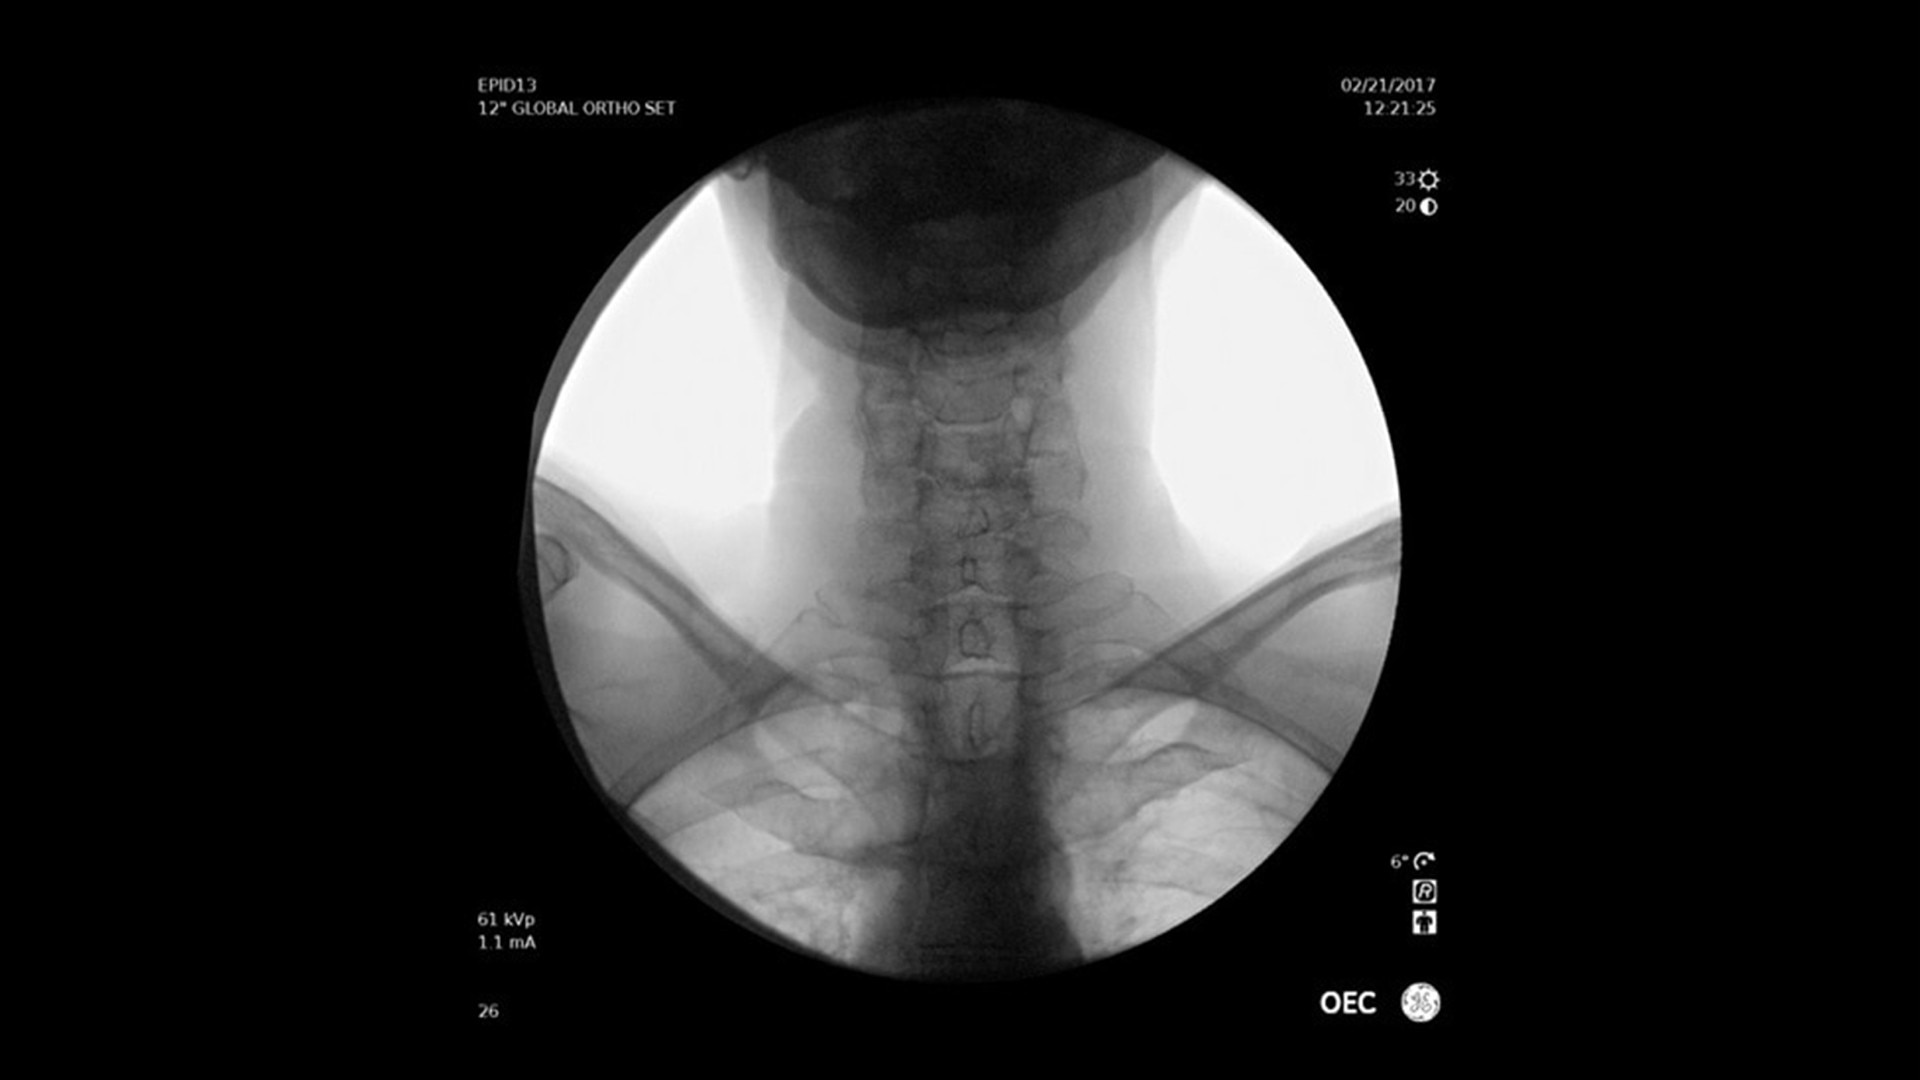

Vielseitig einsetzbar – ideal für orthopädische, gastrointestinale, endoskopische, urologische, neurologische und vaskuläre Eingriffe sowie für die Intensiv- und Notfallmedizin.

Der OEC Elite unterstützt Ihr OP-Team mit fortschrittlicher Bildverarbeitung, die sich dynamisch an klinische Anforderungen anpasst. So entstehen jederzeit präzise und detailreiche Bilder.

Renommierte Bildgebung – mehr sehen, mit weniger Dosis.

Nutzen Sie innovative Funktionen wie Live-Zoom, Digital Pen und vorkonfigurierte Bildprofile – darunter Pädiatrie, General HD und die optionale Bolus-Verfolgung – für eine präzise und schonende Bildgebung.

Im Vergleich zu herkömmlichen Monoblock-C-Bögen ermöglicht der OEC Elite eine bis zu 22 % größere Darstellung anatomischer Strukturen und eine nähere Positionierung des Detektors an der Patientenanatomie.